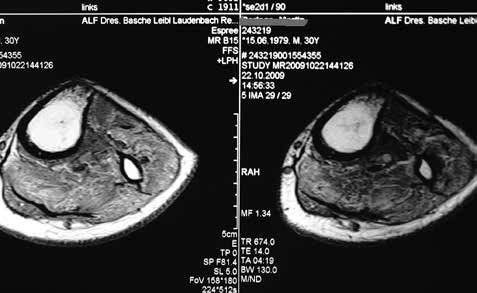

Sehr lange Unterschenkelstümpfe (kurz oberhalb der Spongiosa der distalen Tibia) sind auf die Dauer wegen der Gefahr zunehmender trophischer Störungen über die Jahre auch bei sehr geringem Endkontakt in der Prothese problematisch (Abb. 11). Viele Jahre scheint ein langer US-Stumpf gut versorgbar zu sein, wenn die Amputation im Kindesalter stattfindet und wenn Tibia- und Fibulaende sich fast auf gleicher Höhe befinden und somit eine breitere Auflagefläche für den Endkontakt darstellen (Abb. 12). Gewebe und arterielle Durchblutung stellen sich offenbar im Kindesalter auch besser auf die Gesamtsituation ein. Allgemein gilt aber: Der beste Unterschenkelstumpf ist der, der mit Muskulatur unter physiologischer Vorspannung gedeckt ist.